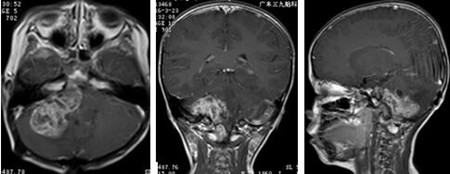

入院后完善术前检查,排除手术禁忌症后,杨宝应主任及其团队为薛仔实施“右侧桥小脑角区及上段脊髓右旁、四脑室内室管膜瘤切除术”,在显微镜下次全切除肿瘤,术后薛仔的症状明显好转,并辅以放化疗。

病理化验诊断:四脑室内室管膜瘤。

▲术前